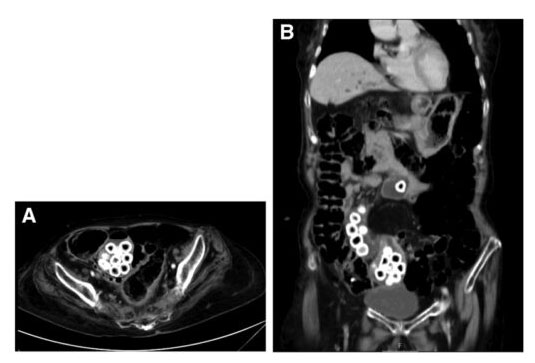

QUIZ: Uma causa incomum de dor abdominal